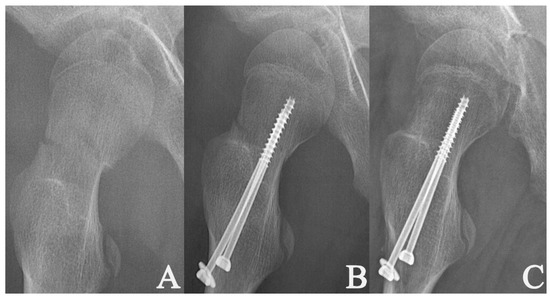

2. Materials and Methods